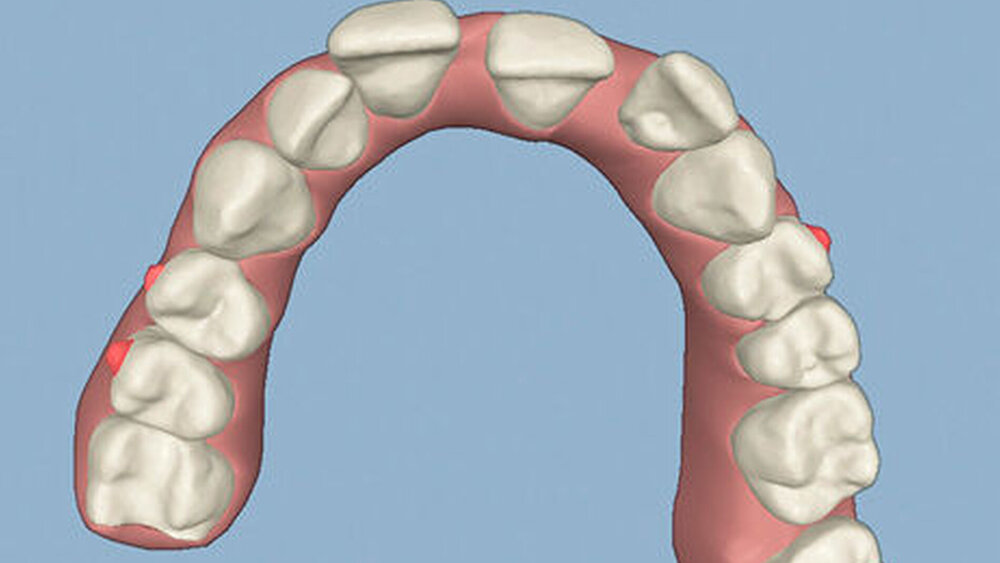

Die Sulkustiefen konnten auf etwas weniger als 4 mm reduziert werden, während der Blutungs- und Plaque-Index bei weniger als 15 Prozent lag. Daher wurde eine kieferorthopädische Behandlung über die nächsten zwei Jahre in Kombination mit engen zahnärztlichen Kontrollen geplant. Als Mittel der Wahl entschieden wir uns gemeinsam mit dem Patienten für das Invisalign-System, da hiermit sowohl eine Schienung als auch eine kraft-arme Bewegung der Zähne möglich sein sollte. Für den Frontzahnbereich wurden keine Attachments geplant, so dass hier eine unnötige Hebelwirkung umgangen werden konnte (Abbildung 3).